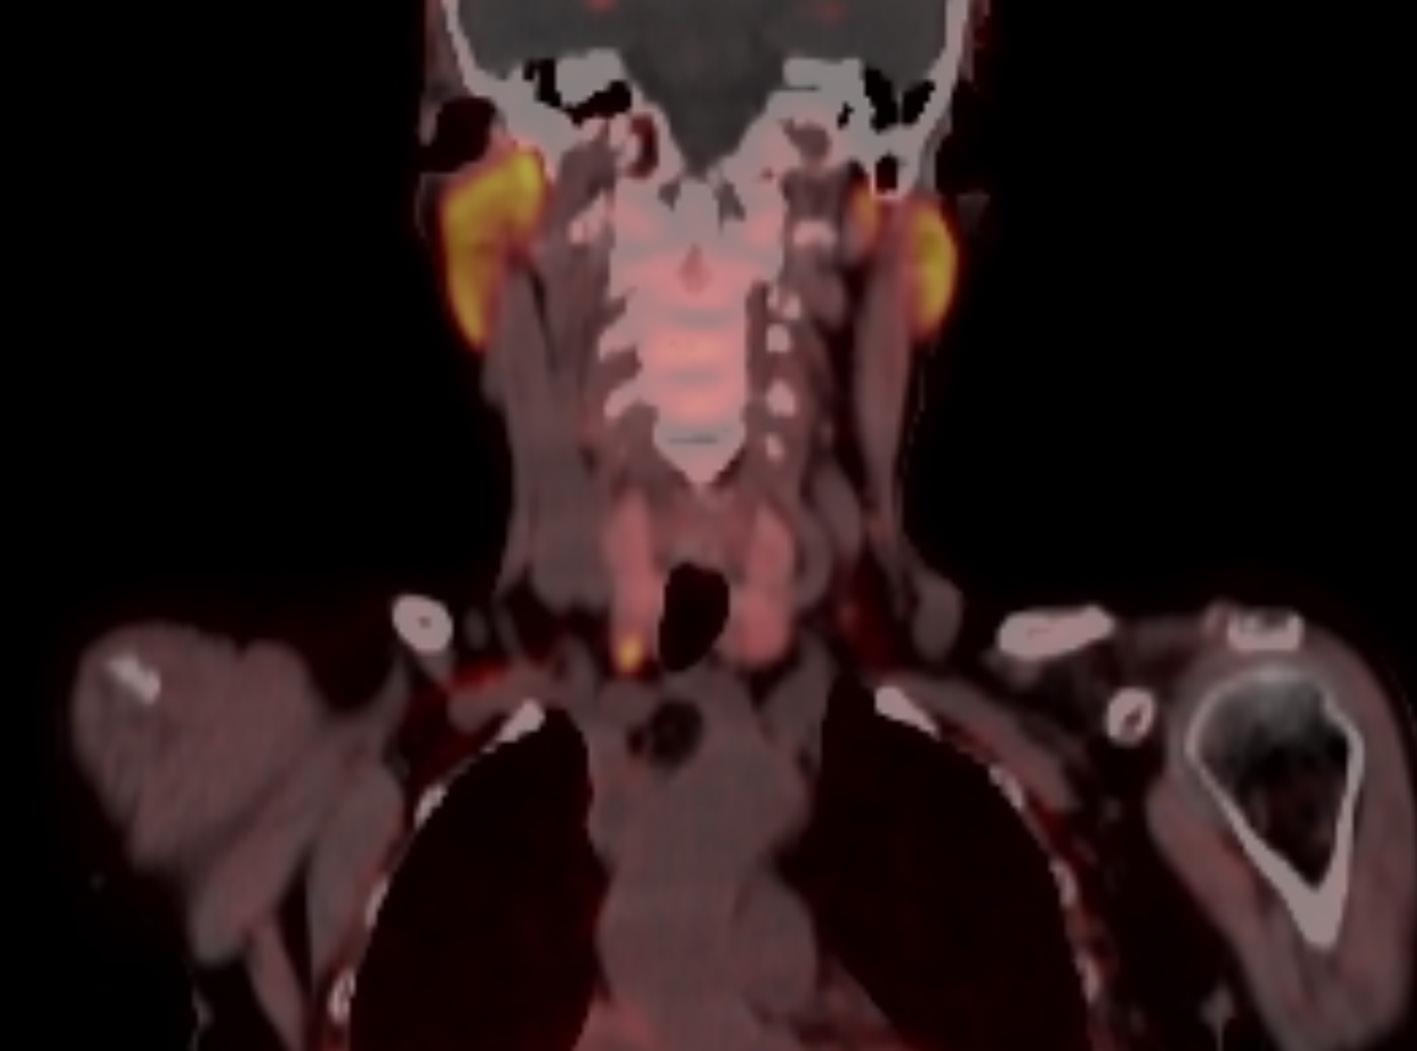

BILDE 1: Initial CT collum viste tumorstørrelse på 70x54 mm. CT undersøkelse en måned senere som var tre dager etter fullført strålebehandling viste tumor-reduksjon til 55x48mm. CT undersøkelse etter ytterligere tre måneder med tillegg av dabrafenib og trametinib viste at tumor hadde gått tilbake til tre cm i størrelse. Samtykke til publisering av røntgenbildene er innhentet fra pasientens ektemann da pasienten er død.

KASUISTIKK 1

En 72 år gammel kvinne oppsøkte fastlegen med nyoppstått 2x2 cm stor kul på halsen. Hun ble henvist til ultralydundersøkelse lokalt og senere ble det utført finnålsprøve samme sted, som ga mistanke om anaplastisk karsinom. Da hadde svulsten vokst til 8 cm. Hun ble henvist til regionsykehus og innlagt neste dag. Grovnålsbiopsier bekreftet anaplastisk thyreoideakarsinom. Pasienten hadde da utviklet heshet og smerter, men hadde ikke svelgvansker eller dyspné. Tumor i thyroidea var inoperabel, samt at hun hadde multiple små lungemetastaser. Det ble startet med strålebehandling to ganger daglig (1,5 GYx30-45) samt ukedose doksorubicin. Behandlingsrespons ble evaluert med CT-undersøkelse (Bilde 1). Det ble påvist BRAF (V600E) mutasjon, og etter fullført strålebehandling ble det startet med BRAF-/MEK hemmerne dabrafenib 75 mg x 1 og trametinib 1 mg x 1 en måned etter innleggelsen. Dosen ble økt etter ni dager. Tumor og metastaser på hals og i lunger viste komplett respons, og pasienten ble operert med venstresidig hemithyreoidektomi etter fem måneder. Det var betydelige adheranser og forandringer rundt thyroidea relatert til tidligere behandling. Endelig histologi viste kun enkeltliggende tumorceller i thyreoidealappen. Dabrafenib 100 mg x 2 og trametinib 2 mg x1 ble kontinuert med enkelte pauser på en til tre uker på grunn av nøytropen feber.